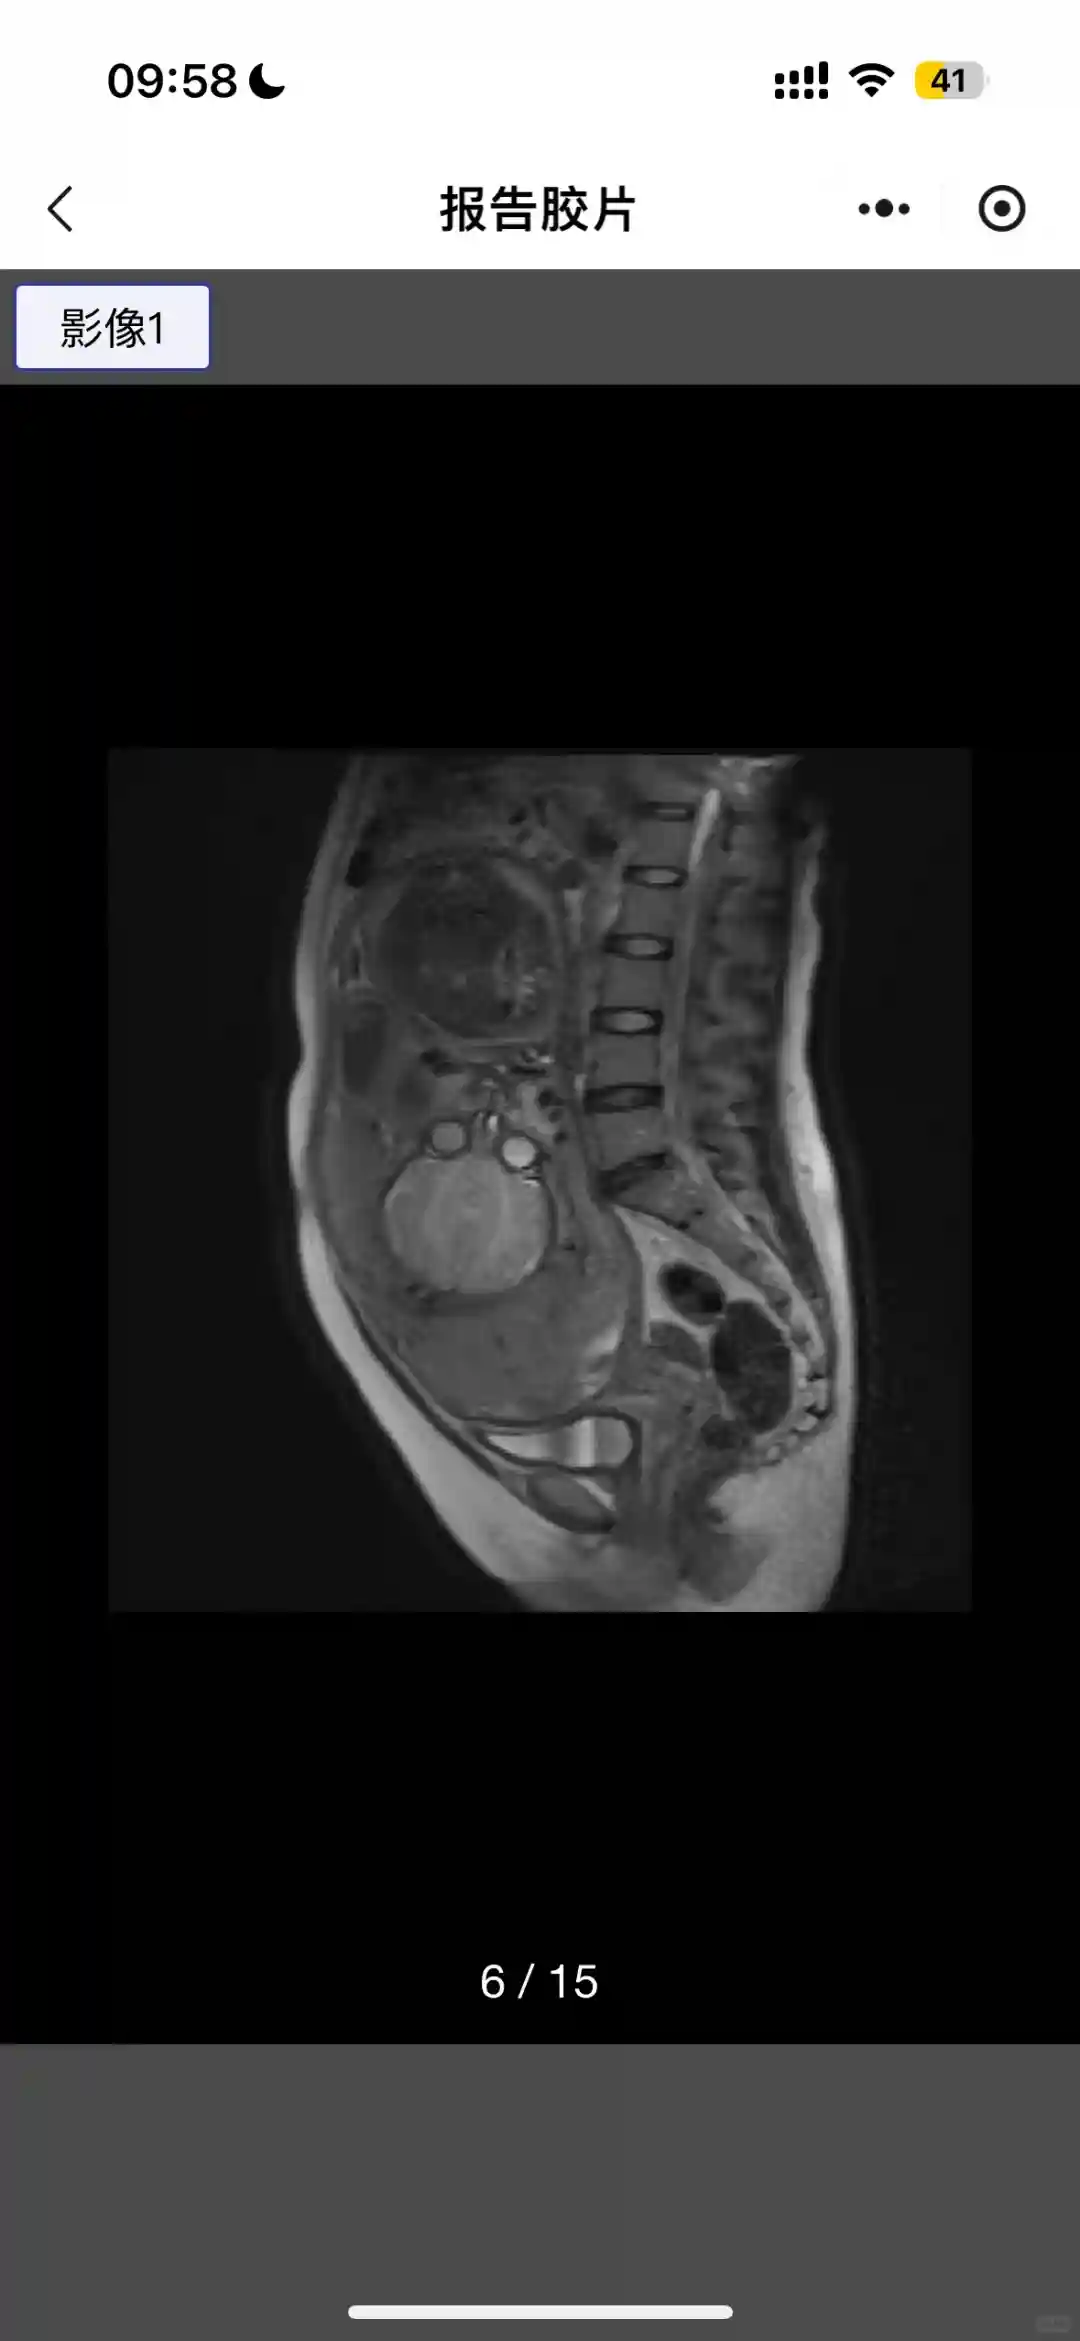

看过我上2篇的都知道我是帆状胎盘➕前置中央胎盘➕部分胎盘植入自身又是抗SSA阳性➕SLE属于buff叠加大满贯,我整个孕期体重增加也没超过20斤,28周小排畸我崽还偏大1周那感动的老母亲真的泪流满面!到了36周➕的生产前检查崽崽就偏小了1周又羊水减少只有2.4但是深度还可以,李教授给的建议是足月前2天生!考虑到可能的情况我不想冒险还是决定听从李教授建议提前2天生,其实我自己是还想拖2天足月37周生。但是又怕不确定因素会影响到崽崽,从被宣布羊水少当天开始我每天醒了就是拍崽崽,互动一下那几天真是胆战心惊!把她抱在手里的瞬间我终于不害怕了,万幸我的小崽崽也很努力,各项指标正常也能够正常吃喝!并且也在平稳成长,希望她继续努力,快快长高高,长壮壮!

总体来说整个孕晚期,常规检查都非常顺利,不管是胎心监测还是常规产检他都平稳通过,更让老母亲欣慰的是崽崽居然在36周自己变成了头位,如果不是老母亲buff叠加崽崽肯定会更健康!因为我的原因小崽崽做了2次心脏彩超但是都没啥问题。提示的三尖瓣返流也在最后的B超消失了!只能说小棉袄非常贴心!各位姐妹有相关问题也可以滴我能偷玩手机的时候我都会回复呢!我们月子篇再见啦!#孕晚期 #剖腹产 #李家福